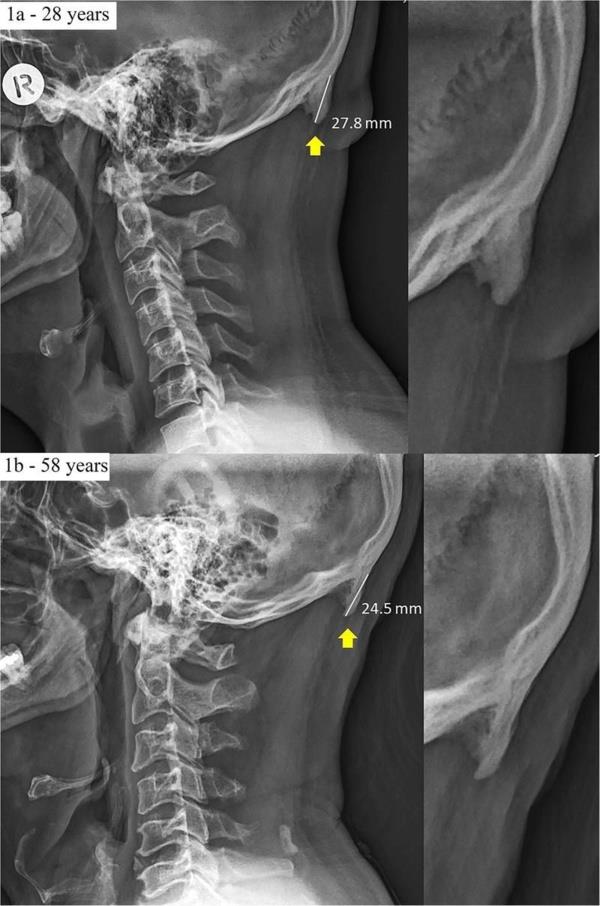

2. Avustralya’daki Sunshine Coast Üniversitesi’den bilim adamları Dr. David Shahar ve Prof. Mark Sayers, 18-30 yaş arasındaki 218 kişinin röntgen çekimlerini inceledi. Yapılan araştırmalar sonucu röntgen çekilen kişilerin neredeyse yarısının kafatası şeklinin yoğun cep telefonu ve tablet kullanımına bağlı olarak ‘değiştiği’, boynuzumsu bir çıkıntıya benzediği belirtildi.

Avustralya’daki Sunshine Coast Üniversitesi’den bilim adamları Dr. David Shahar ve Prof. Mark Sayers, 18-30 yaş arasındaki 218 kişinin röntgen çekimlerini inceledi. Yapılan araştırmalar sonucu röntgen çekilen kişilerin neredeyse yarısının kafatası şeklinin yoğun cep telefonu ve tablet kullanımına bağlı olarak ‘değiştiği’, boynuzumsu bir çıkıntıya benzediği belirtildi.

3. Yapılan araştırmaya göre, gününün büyük kısmında teknolojik aletlere kafasını eğerek bakan gençlerin, kafatasındaki oksipital kemik denen bölge, görünür şekilde belirginleşmeye başlıyor.

Yapılan araştırmaya göre, gününün büyük kısmında teknolojik aletlere kafasını eğerek bakan gençlerin, kafatasındaki oksipital kemik denen bölge, görünür şekilde belirginleşmeye başlıyor.

4. Her 4 gençten birinde görülen bu durum, dijital ekranlar karşısında geçirilen süreyle ilgili endişelere bir yenisini daha ekliyor.

Her 4 gençten birinde görülen bu durum, dijital ekranlar karşısında geçirilen süreyle ilgili endişelere bir yenisini daha ekliyor.

6. Ensenin üstünde sivrilen 10-30 milimetre arasında değişen çıkıntıya, &#8216;dış oksipital kabartı&#8217; deniyor. Dış oksipital kabartıya, taşınabilir dijital cihazlar yaygınlaşmaya başlamadan önce daha çok yaşlı insanlarda rastlandığı, gençlerde ise oldukça nadiren rastlandığı belirtiliyor.

Ensenin üstünde sivrilen 10-30 milimetre arasında değişen çıkıntıya, ‘dış oksipital kabartı’ deniyor. Dış oksipital kabartıya, taşınabilir dijital cihazlar yaygınlaşmaya başlamadan önce daha çok yaşlı insanlarda rastlandığı, gençlerde ise oldukça nadiren rastlandığı belirtiliyor.